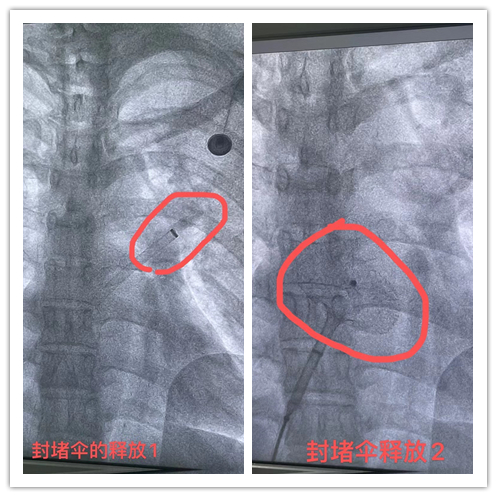

在与患者做好充分的术前准备后,由张曹进主任及李勇主任、黄生华主治医师进行介入手术,心血管内科团队互相配合,术中局部麻醉,从大腿根部的股静脉做一个穿刺,仅在患者身上切开一小道的伤口,由此引入封堵器装置,在透视下及超声检查下证实房间隔缺损封堵器位置良好,房缺完全封堵,无残余分流。手术仅半小时,就顺利完成手术,术后患者转入CCU监护治疗。

李勇主任表示,房间隔封堵术采用经股静脉穿刺的办法,将封堵伞片送至心房,修补位于左右心房间的缺损处,阻断心房水平的左向右分流,恢复正常的血液循环。相较于房间隔修补术,房间隔封堵术其优点是创口小,痛苦小,恢复快,避开了开胸、体外循环、心脏停跳等环节,手术全程由超声引导,实时了解心脏情况,判断手术效果,手术成功率高,现已广泛成熟应用于临床,房间隔缺损、室间隔缺损、动脉导管未闭等先天心脏疾病,均可以采取介入封堵方式治疗。

房间隔缺损封堵术示意图